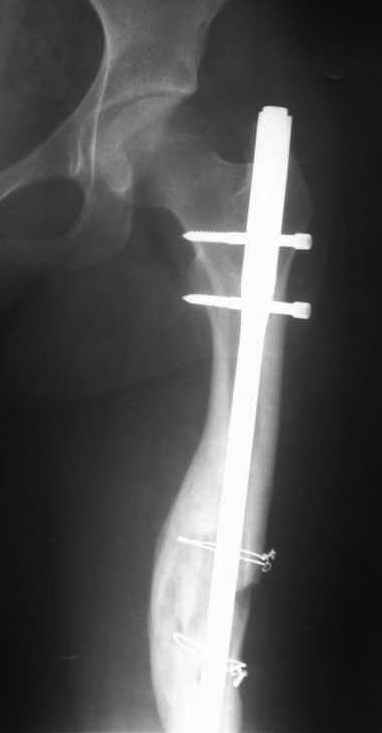

Здравствуйте коллеги. Сегодня поступил юноша 13 лет с повторным переломом правого бедра на стержне. Первый перелом был зимой 2003 году, синтезирован 2-мя стержнями Богданова. В июне 2003 года миграция стержней - стержни убраны. Повторный перелом в декабре 2003 года. Произведён МОС стержнем. Сегодня повторный перелом на стержне. Конечность уложена на шину Беллера. Господа, как можно удалить данный стержень? Чем предпочтительнее, на Ваш взгляд, синтезировать данный перелом у молодого растущего юноши с ожирением П ст.: пластиной, простым стержнем или стержнем с блокированием? ЭОПа у нас нет, поэтому пользуемся наборами ДЕОСТа с дистальной навигацией.

Снимок только при поступлении один.

Image(037)кор.jpg

22KB (23181 bytes)